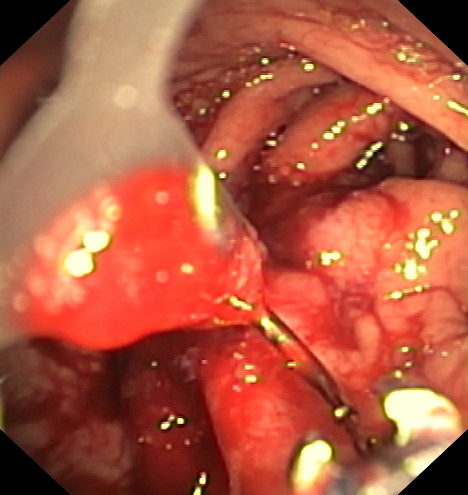

La gastroplastia endoscópica mediante la técnica endomanga se realiza por el gastroscopia, bajo anestesia general y dura aproximadamente entre 25 y 35 minutos. Mediante la endoscopia se realizan unos 18 pliegues definitivos a lo largo de todo el cuerpo gástrico, reduciendo de manera importante su capacidad de apertura, acortándolo y estrechándolo. Gracias a esta reducción los pacientes disminuyen la sensación de hambre.

Mediante un sistema de sutura acoplado a un endoscopio, se sutura el estómago “desde dentro” dándole un aspecto similar al conseguido por la cirugía de gastrectomía vertical laparoscópica (manga gástrica quirúrgica), pero con menor riesgo quirúrgico y muy buenos resultados a medio y largo plazo. De esta manera se limita la cantidad de comida que puede entrar en el estómago e igualmente hace que la digestión sea más lenta, favoreciendo enormemente la saciedad y la pérdida de peso. Es una técnica definitiva, pero por vía oral, ni realizar heridas abdominales ni cicatrices.